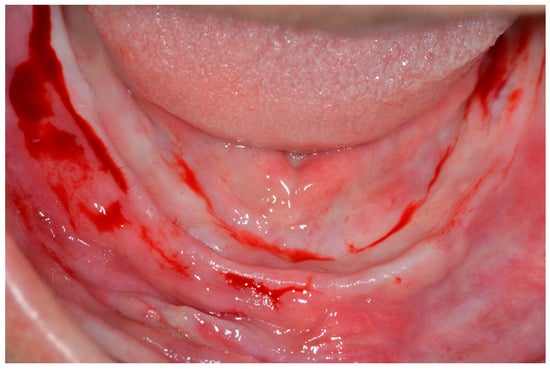

A supra-crestal incision was made in the first molar region, and two vertical releasing incisions were made in the first molar region. A mucoperiosteal flap was made and deflected, allowing the anatomical structures to be visualized [19] (Figure 3).

Figure 3.

View of the mandible after elevating the mucoperiosteal flap.